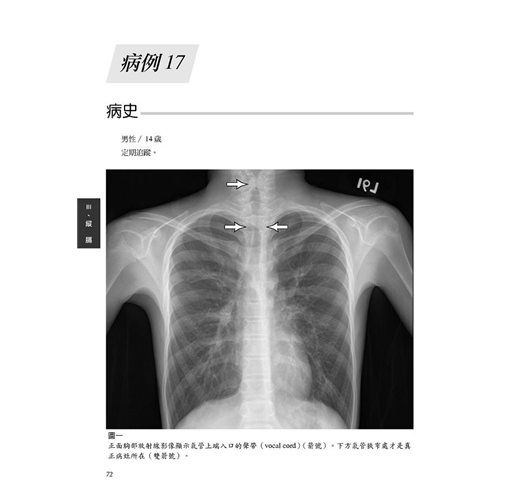

病例17 氣管狹窄(Tracheal stenosis)∕氣管插管後之後遺症 72

病例18 甲狀腺乳突癌合併氣管侵犯 76